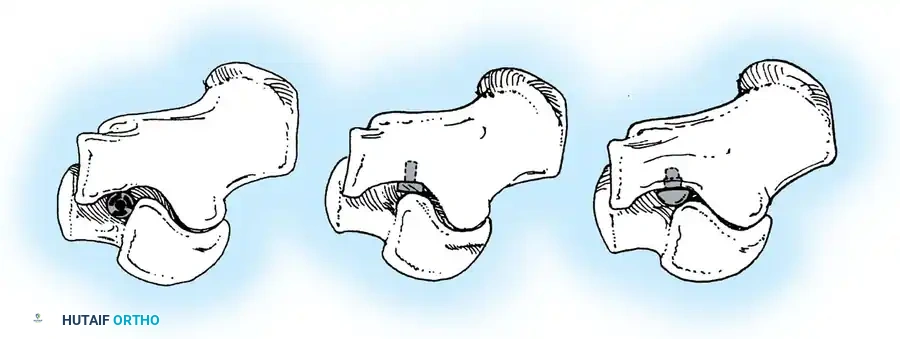

جراحة إزالة التحام الكاحل والعقب

تُجرى هذه العملية عادة للمرضى الأصغر سناً (10 إلى 15 عاماً) عندما يكون الالتحام في المفصل الأوسط (Middle Facet) صغيراً (أقل من 50% من مساحة المفصل) ولا توجد علامات على خشونة المفاصل.

يتم الدخول جراحياً من الجهة الداخلية للقدم، ويتم استئصال الجسر العظمي بدقة باستخدام أدوات دقيقة حتى يظهر الغضروف السليم للمفصل. كما هو الحال في الالتحام السابق، يتم وضع نسيج دهني أو شمع عظمي لمنع الالتصاق مجدداً.

* الدمج الثلاثي (Triple Arthrodesis): يتم فيه دمج ثلاثة مفاصل رئيسية في الجزء الخلفي من القدم وتثبيتها بمسامير طبية لتلتحم كعظمة واحدة. يزيل هذا الإجراء الألم تماماً ويصحح شكل القدم، ولكنه يلغي الحركة في هذه المفاصل.

* دمج المفصل تحت الكاحل (Subtalar Arthrodesis): دمج مفصل واحد فقط إذا كانت الخشونة مقتصرة عليه.